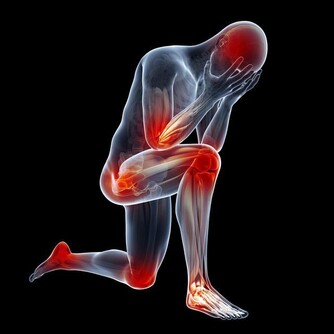

他汀和幾乎所有的藥物一樣,都存在著潛在都副作用,這是所有藥物的兩面性。我們需要正確看待並監測副作用

他汀最常見的副作用就是引起肝臟功能損害,